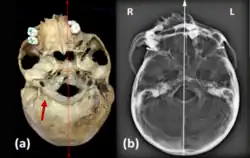

Na vista inferior o crânio apresentava assimetria de todo o maciço facial com deslocamento muito significativo do plano sagital mediano (figura 2).

Na norma posteroinferior nota-se uma fusão atlanto-occipital (figura 2), com fusão do maciço lateral e um arco posterior de aparência normal do atlas. O processo odontóide também se encontra fundido com o arco anterior e a massa lateral direita do atlas, para além disso, é ainda observável uma sinostose do canal vertebral.

Um esqueleto de um individuo com cerca de 25 anos que foi um soldado do exército real jugoslavo, apresenta fusão do atlas e do áxis o que causava limitação na rotação do pescoço, identificada como síndrome de Klippel-Feil tipo II (Leggio e colaboradores, 2022)[10]. Na análise craniana verificou-se uma assimetria do parietal e occipital causando deformação no crânio, observou-se também uma hipoplasia condilar occipital bilateral e assimétrica do foramen magnum (figura 4), onde se verifica que, embora os côndilos estejam completos estes são assimétricos e deve-se à fusão das vértebras anteriormente referidas. Há também um desvio no septo nasal (figura 4), mas pode ter ocorrido devido a outros fatores que não a síndrome. Analisando a coluna vertebral, verificou-se que este individuo tinha escoliose e spina bifida occulta, sendo estes sintomas da síndrome de Klippel-Feil (tal com citado em Leggio et al, 2022)[10].